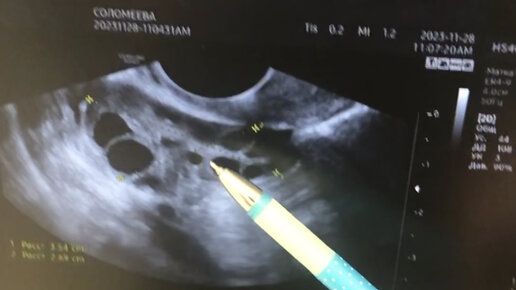

Мультифолликулярные яичники и планирование беременности

Мультифолликулярные яичники являются одним из частых обращений среди женщин с нарушениями цикла и задержками менструаций. Самый первый симтом-нарушение цикла, точнее его удлинение. Но часто этот диагноз ставится запоздало. Потому что с самого начала девушка привыкла, что у нее менструации не приходят во время, есть нарушение цикла, а когда встал вопрос о рождении малыша, длинный перерыв между месячными, менструации 1 раз в 3 месяца стали уже проблемой. Как избавиться от мультифолликулярных яичников? Чаще всего женщинам просто “вызывают” менструации, не вникая в суть проблемы...